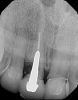

Fig 4. Radiograph of the implant to replace the tooth in Fig 3 (implant placed by David Levine, DDS).

Figure 4